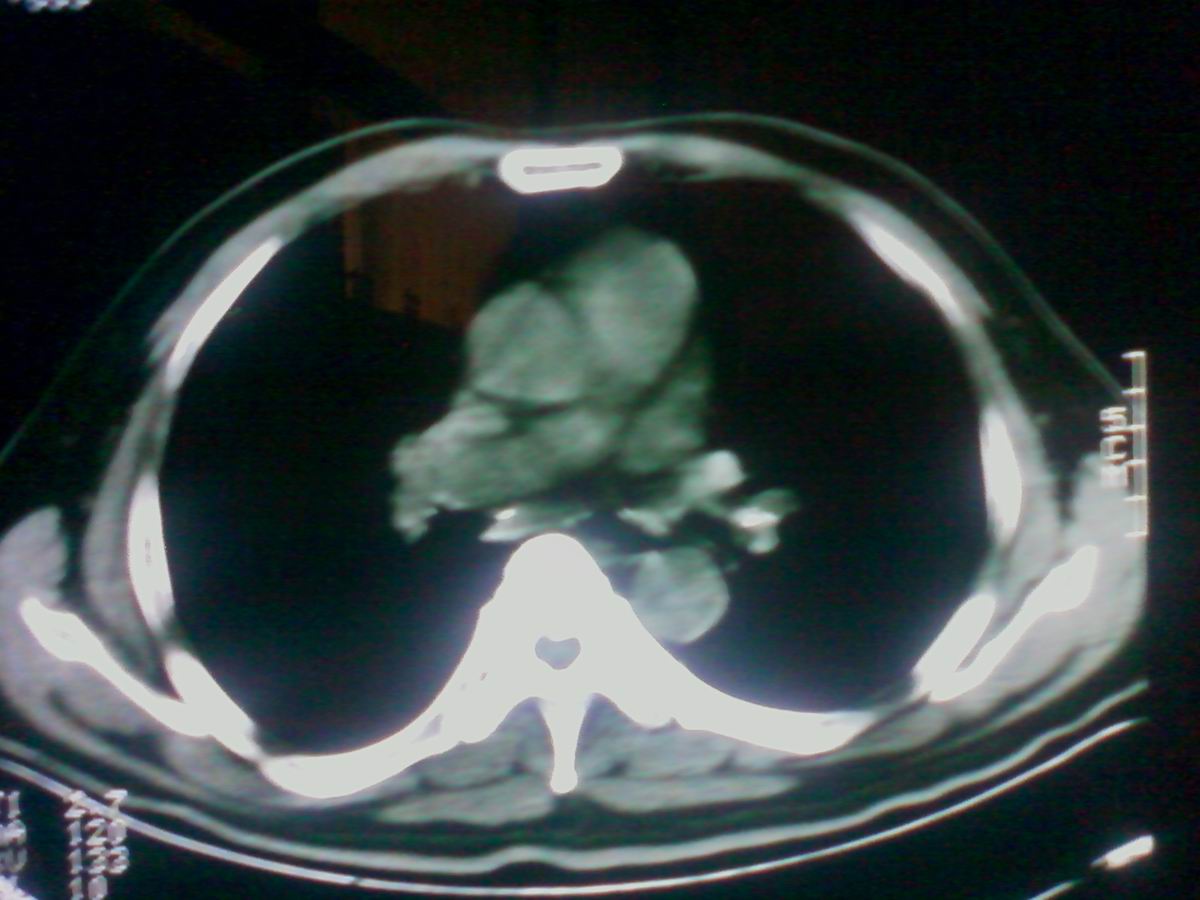

标题: CT25801:患者男性,65岁,临床提示双肺可闻及广泛罗音,看 [打印本页]

标题: CT25801:患者男性,65岁,临床提示双肺可闻及广泛罗音,看

气管后部见半圆形软组织密度病灶,考虑占位,建议气管镜除外鳞癌。

气管上段的肿瘤多为良性乳头状瘤,气管下段的肿瘤多为鳞癌,气管中段的良恶性各占一半。本例位于气管下段,先按恶性处理。不过纤支镜是免不了的。